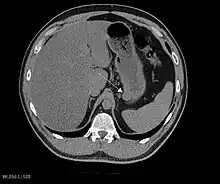

CT scanning is often undertaken (see the radiology section).

The purpose of radiologic imaging is to locate the lesion, evaluate for signs of invasion and detect metastasis. Features of GIST vary depending on tumor size and organ of origin. The diameter can range from a few millimeters to more than 30 cm. Larger tumors usually cause symptoms in contrast to those found incidentally which tend to be smaller and have better prognosis.[4][13] Large tumors tend to exhibit malignant behavior but small GISTs may also demonstrate clinically aggressive behavior.[14]

Barium fluoroscopic examinations and CT are commonly used to evaluate the patient with abdominal complaints. Barium swallow images show abnormalities in 80% of GIST cases.[14] However, some GISTs may be located entirely outside the lumen of the bowel and will not be appreciated with a barium swallow. Even in cases when the barium swallow is abnormal, an MRI or CT scan must follow since it is impossible to evaluate abdominal cavities and other abdominal organs with a barium swallow alone. In a CT scan, abnormalities may be seen in 87% of patients and it should be made with both oral and intravenous contrast.[14] Among imaging studies, MRI has the best tissue contrast, which aids in the identification of masses within the GI tract (intramural masses). Intravenous contrast material is needed to evaluate lesion vascularity.

Preferred imaging modalities in the evaluation of GISTs are CT and MRI,[16]: 20–21 and, in selected situations, endoscopic ultrasound. CT advantages include its ability to demonstrate evidence of nearby organ invasion, ascites, and metastases. The ability of an MRI to produce images in multiple planes is helpful in determining the bowel as the organ of origin (which is difficult when the tumor is very large), facilitating diagnosis.

As the tumor grows it may project outside the bowel (exophytic growth) and/or inside the bowel (intraluminal growth), but they most commonly grow exophytically such that the bulk of the tumor projects into the abdominal cavity. If the tumor outstrips its blood supply, it can necrose internally, creating a central fluid-filled cavity with bleeding and cavitations that can eventually ulcerate and communicate into the lumen of the bowel. In that case, barium swallow may show an air, air-fluid levels or oral contrast media accumulation within these areas.[14][17] Mucosal ulcerations may also be present. In contrast-enhanced CT images, large GISTs appear as heterogeneous masses due to areas of living tumor cells surrounding bleeding, necrosis or cysts, which is radiographically seen as a peripheral enhancement pattern with a low attenuation center.[13] In MRI studies, the degree of necrosis and bleeding affects the signal intensity pattern. Areas of bleeding within the tumor will vary its signal intensity depending on how long ago the bleeding occurred. The solid portions of the tumor are typically low signal intensity on T1-weighted images, are high signal intensity on T2-weighted images and enhanced after administration of gadolinium. Signal-intensity voids are present if there is gas within areas of necrotic tumor.[15][18][19]

Malignancy is characterized by local invasion and metastases, usually to the liver, omentum and peritoneum. However, cases of metastases to bone, pleura, lungs and retroperitoneum have been seen. In distinction to gastric adenocarcinoma or gastric/small bowel lymphoma, malignant lymphadenopathy (swollen lymph nodes) is uncommon (<10%) and thus imaging usually shows absence of lymph node enlargement.[13] If metastases are not present, other radiologic features suggesting malignancy include: size (>5 cm), heterogeneous enhancement after contrast administration, and ulcerations.[4][13][20] Also, overtly malignant behavior (in distinction to malignant potential of lesser degree) is less commonly seen in gastric tumors, with a ratio of behaviorally benign to overtly malignant of 3-5:1.[4] Even if radiographic malignant features are present, these findings may also represent other tumors and definitive diagnosis must be made immunochemically.